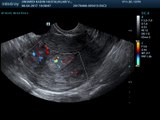

Hidrosonografi Endometrial Polip

ENDOMETRİAL POLİP (ULTRASON)